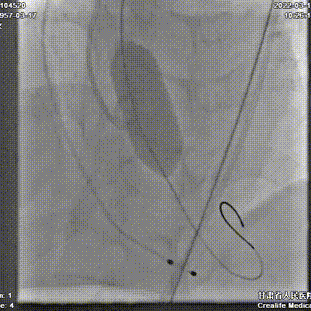

术中剪影:

手术影像:

主动脉根部造影

瓣叶增厚,中度反流

TaurusAtlas 20mm球囊预扩

冠脉灌注良好,无腰征

第一次定位释放

第一次释放后位置尚可

静待5分钟后位置明显下滑

回收调整超硬导丝后,再次定位

逐步释放瓣膜,工作位位置理想

工作位造影

瓣膜充分膨胀,完全释放

植入后位置理想,无反流